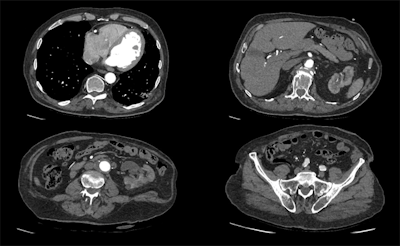

A 100-kV CT scan with a dose length product of 159.8 mGy.cm, using Canon's Advanced Intelligent Clear-IQ Engine (AiCE). Image courtesy of Radboud UMC, Nijmegen, the Netherlands.Agfa HealthCare is directing attention to augmented and AI technology included in its digital radiography systems and Musica image processing software.